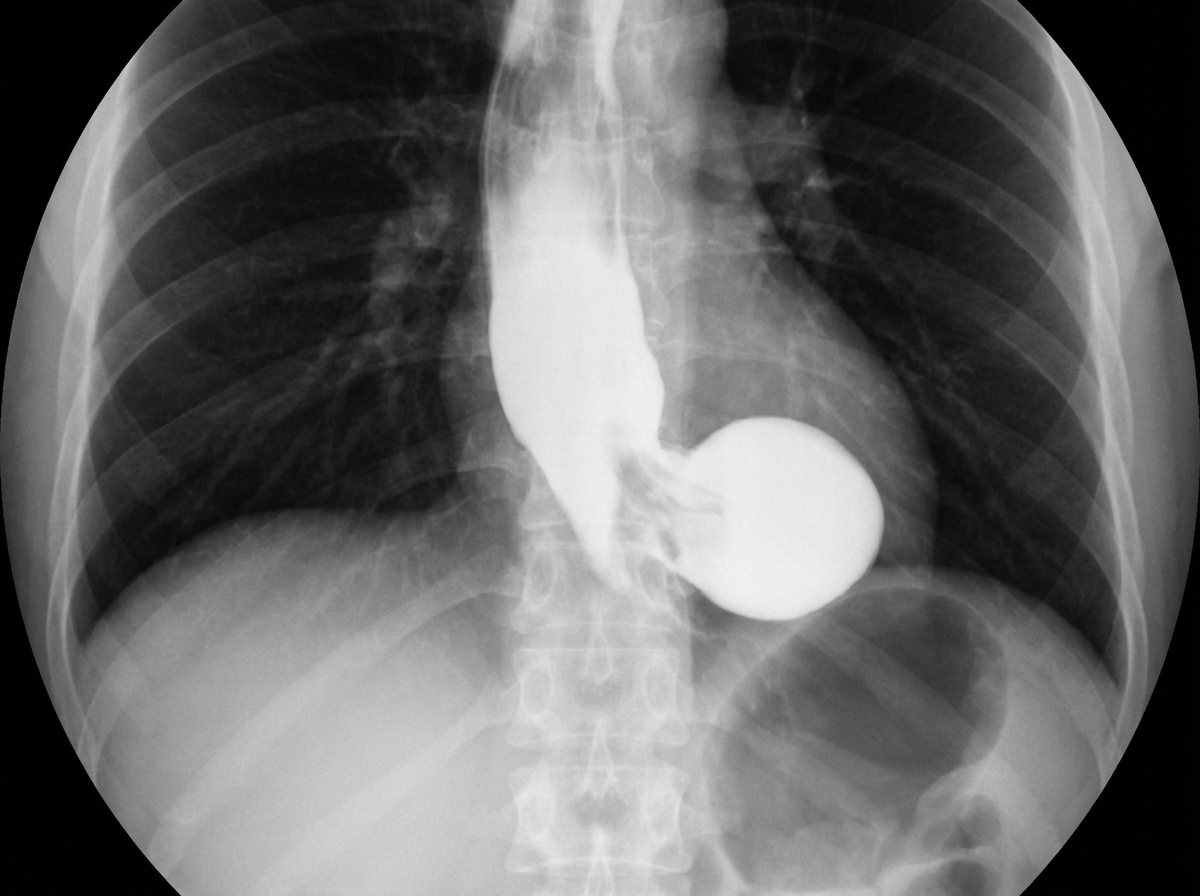

A 65-year-old patient presents with dysphagia and regurgitation. Barium swallow imaging is provided. What is the diagnosis?

Explanation: ***Epiphrenic diverticulum*** - Located in the **distal esophagus** just above the **diaphragm**, which would be clearly visible on barium swallow imaging as a pouch-like outpouching in the lower third of the esophagus. - Commonly presents with **dysphagia** and **regurgitation** in elderly patients due to impaired esophageal motility and increased intraluminal pressure. *Paraesophageal hernia* - Involves herniation of the **gastric fundus** through the **diaphragmatic hiatus** alongside the esophagus, appearing as stomach contents above the diaphragm on barium swallow. - Typically presents with **chest pain** and **early satiety** rather than primarily dysphagia and regurgitation. *Zenker's diverticulum* - Located in the **hypopharynx** at the **pharyngoesophageal junction** (upper esophageal sphincter level), appearing much higher on barium swallow imaging. - Presents with **halitosis**, **nocturnal coughing**, and regurgitation of **undigested food**, often with a palpable neck mass. *Diaphragmatic hernia* - Shows **abdominal organs** (stomach, bowel) displaced into the **thoracic cavity** through a diaphragmatic defect on imaging. - More commonly presents with **respiratory symptoms** and **chest pain** rather than isolated dysphagia and regurgitation.

Explanation: **Explanation:** **Killian’s Dehiscence** is a weak triangular area in the posterior wall of the pharynx. It is located **between the two components of the inferior constrictor muscle**: 1. **Thyropharyngeus:** The upper oblique fibers. 2. **Cricopharyngeus:** The lower horizontal fibers (which act as the upper esophageal sphincter). The correct answer is **B** because this dehiscence represents a potential gap where the pharyngeal mucosa can herniate due to increased intrapharyngeal pressure, leading to the formation of a **Zenker’s Diverticulum** (Pulsion diverticulum). **Analysis of Incorrect Options:** * **Option A:** The area below the superior constrictor (Sinus of Morgagni) is where the Eustachian tube and levator veli palatini enter; it is not the site of Killian’s dehiscence. * **Option C:** The area below the cricopharyngeus is known as **Killian-Jamieson area**. Herniation here results in a Killian-Jamieson diverticulum, which is lateral, not posterior. * **Option D:** The upper one-third of the esophagus consists of skeletal muscle, not smooth muscle. This anatomical landmark is unrelated to pharyngeal pouches. **High-Yield Clinical Pearls for NEET-PG:** * **Zenker’s Diverticulum:** Always emerges through Killian’s dehiscence. It is a **false diverticulum** (contains only mucosa and submucosa). * **Symptoms:** Dysphagia, regurgitation of undigested food, halitosis (foul breath), and a "gurgling" sound in the neck. * **Boyce’s Sign:** Swelling in the neck (usually left side) that gurgles on compression. * **Investigation of Choice:** Barium Swallow (shows a pouch behind the esophagus). * **Treatment:** Endoscopic Dohlman’s procedure (stapling) or open diverticulectomy with cricopharyngeal myotomy.